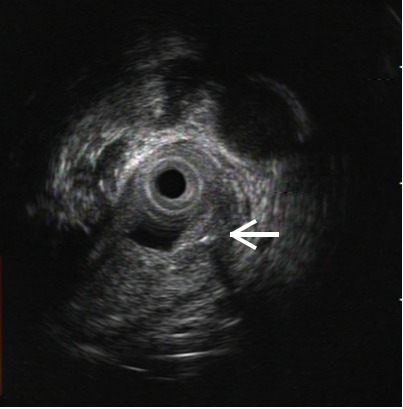

相对于食管腔而言,鱼刺太细,且可能不断移动。尽管有CT图像辅助,但仍无法直接帮助内镜定位,用内镜在黏膜下层寻找,无异于大海捞针。为此,耳鼻喉科、麻醉科、超声科、影像科和消化内镜中心的专家们组织了多学科讨论,决定采用气管插管麻醉,以内镜隧道技术联合术中超声内镜进行食管黏膜下切开探查。由于需要动用多种内镜设备,搬动到大手术室十分不便,麻醉科决定为内镜中心提供麻醉设备支持,在内镜中心完成气管插管,为手术提供更便利的条件。

但手术远比想像中更为困难,由于解剖结构的因素,内镜在高位食管建立黏膜下隧道本来就有很高难度,还要在狭窄的隧道内完成超声内镜检查,既不能发生食管穿孔,又要准确定位鱼刺,挑战十分严峻。内镜中心多位医生轮番上阵,在护理团队娴熟配合下,经过长达数小时的地毯式搜寻,终于发现鱼刺的踪迹。鉴于已发生过取出过程夹断鱼刺的情况,为保证鱼刺完整,在反复超声探查判断术中引发鱼刺穿破食管的可能性不大后,医生们采用了一种新办法:在鱼刺远端的食管黏膜再切开一道深度接近肌层的小切口,然后自鱼刺近端建好的黏膜下隧道再次进镜,终于将这根长约2.4cm的“流浪”鱼刺完整地从远端的切口里“推赶”了出去。